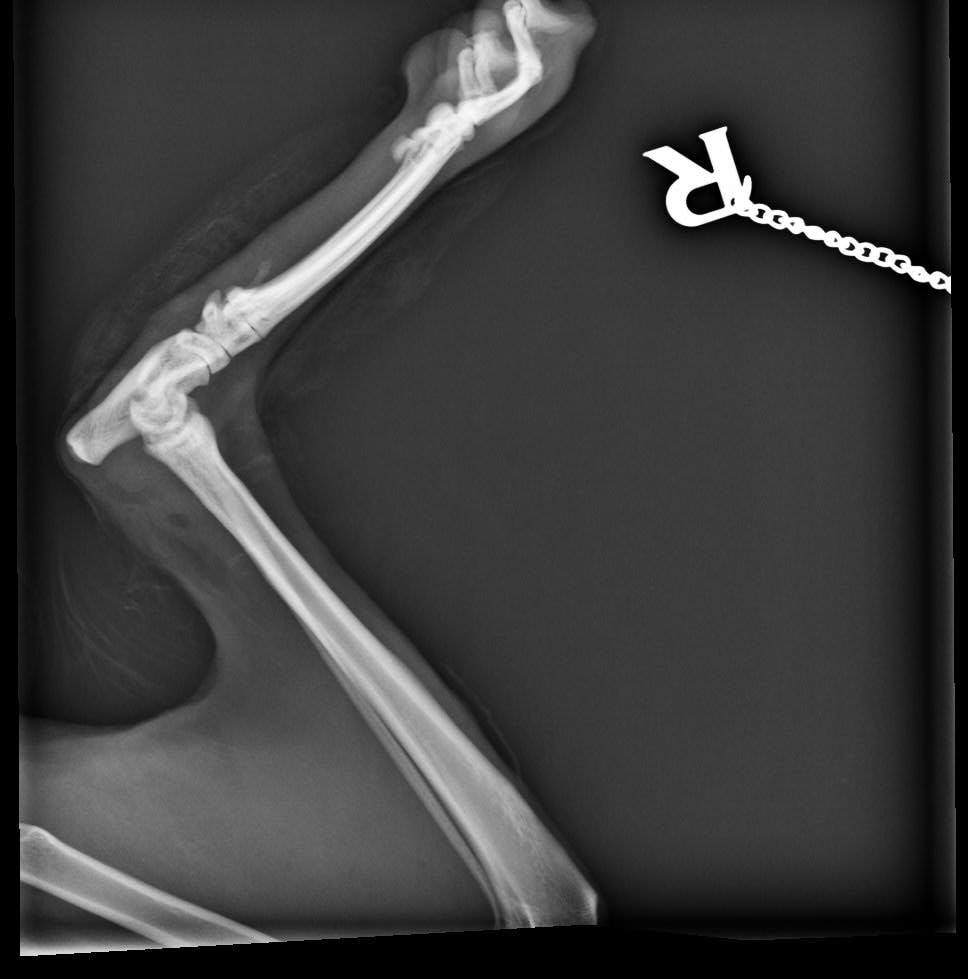

Hodně moc málo. Bílé vem čert, bude za nimi asi stát zánět z rány, který zasáhl i kost a kloub a mnoho dalších zranění které má po těle.

🔸Ocásek je naštěstí vážně zlomený jen 1x. To ostatní jsou jen "šrámy a prkotiny". Zvládli jsme i SONO a RTG.